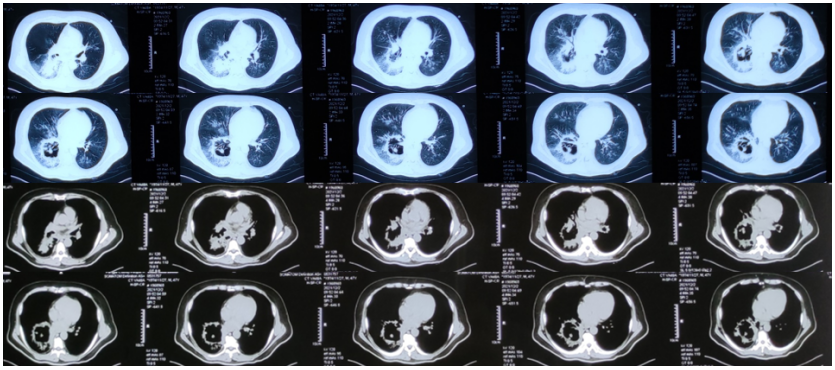

11天复查胸部CT:气管连续性受损及气管旁积气;左、右主支气管壁局限性不连续,气管纵隔瘘可能;双肺肺炎,右下为甚,右侧胸腔积液,右肺下叶受压不张,右肺下叶薄壁囊腔并气液平,考虑感染性病变(图9)

图片

图9  复查胸部CT